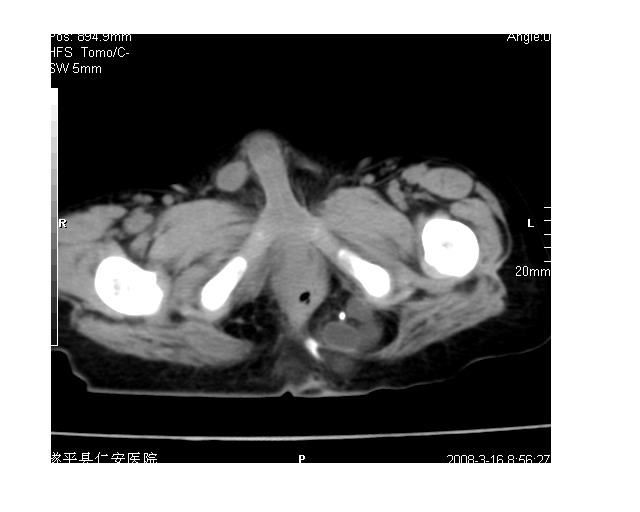

以下是引用lkc8963在2008-3-16 12:49:00的发言:[br]盆底巨大混杂密度肿块,富含多种组织成分包括脂肪/液体/软组织/钙化,边界清楚,向前压迫肠管及膀胱,向后突入骶尾部皮下脂肪层,首先考虑畸胎瘤,诊断时需要与脊柱裂/囊性淋巴管瘤等区别。